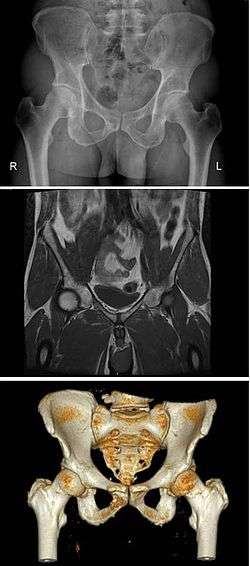

The pelvis (plural pelves or pelvises) is either the lower part of the trunk of the human body[1] between the abdomen and the thighs (sometimes also called pelvic region of the trunk) or the skeleton embedded in it[2] (sometimes also called bony pelvis, or pelvic skeleton).

The pelvic region of the trunk includes the bony pelvis, the pelvic cavity (the space enclosed by the bony pelvis), the pelvic floor, below the pelvic cavity, and the perineum, below the pelvic floor.[1] The pelvic skeleton is formed in the area of the back, by the sacrum and the coccyx and anteriorly and to the left and right sides, by a pair of hip bones. The two hip bones connect the spine with the lower limbs. They are attached to the sacrum posteriorly, connected to each other anteriorly, and joined with the two femurs at the hip joints. The gap enclosed by the bony pelvis, called the pelvic cavity, is the section of the body underneath the abdomen and mainly consists of the reproductive organs (sex organs) and the rectum, while the pelvic floor at the base of the cavity assists in supporting the organs of the abdomen.

In mammals, the bony pelvis has a gap in the middle, significantly larger in females than in males. Babies pass through this gap when they are born.